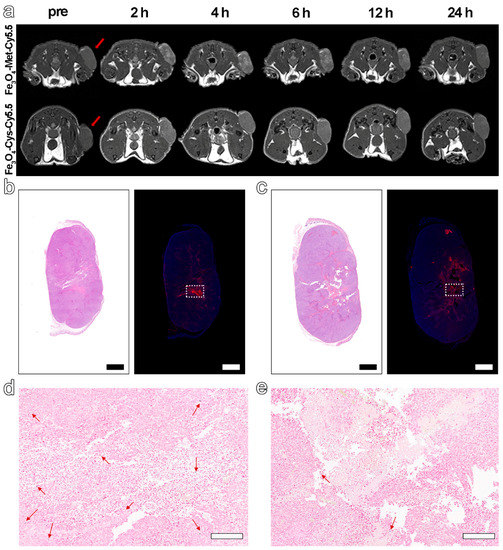

As the hypoxic areas in tumors may change slightly over time, the MRI was scanned again with the termination at the highest signal value (6 h) to further explore the ability of Fe3O4-Met-Cy5.5 to visualize hypoxia distribution. As expected, we found a highly brightening contrast again in the central region of the tumor treated with Fe3O4-Met-Cy5.5 (Figure 5a), and its signal value at 6 h was 1.40-fold higher than that of Pre (Figure 5b). However, the brightening effect was much weaker in the control group, and its signal value was only a 1.14-fold enhancement. As shown in Figure 5c,d, there were obvious positive areas in the center of the tumor, and the positive areas in the Fe3O4-Met-Cy5.5 group were well-consistent with the signal-enhanced regions in the MRI images at 6 h. In addition, the expression of HIF-1α in the central areas was significantly stronger than that of the surrounding less-hypoxic areas (Figure S8b). The above results indicated that the Fe3O4-Met-Cy5.5 probe can achieve T1-weighted MRI of hypoxic areas in tumors. Moreover, Prussian blue staining results demonstrated that the number of blue spots for the tumor treated with Fe3O4-Met-Cy5.5 was significantly larger than that of the control group (Figure 5e,f), further proving the higher accumulation and retention of Fe3O4-Met-Cy5.5 in hypoxic tumors. Anyway, the H&E staining (Figure S9) of both groups showed no obvious pathological symptoms of inflammation, cell edema, and necrosis in the tissues of tumor-bearing mice, indicating the biosafety of the two nanoprobes at the dosage of 5.6 mg Fe kg−1.

Figure 5.

(a) T1-weighted MRI of tumor-bearing mice before (pre) and 6 h post-injection of Fe3O4-Met-Cy5.5 or Fe3O4-Cys-Cy5.5. (b) The MRI signals at the time before (pre) and after (6 h) injection of Fe3O4-Met-Cy5.5 or Fe3O4-Cys-Cy5.5. H&E staining (left) and immunofluorescence staining (right) for tumors of mice injected with Fe3O4-Met-Cy5.5 (c) or Fe3O4-Cys-Cy5.5 (d) (scale bars represent 1000 μm). Prussian blue staining of hypoxic area (dashed area on immunofluorescence staining images) in the tumors of mice treated with Fe3O4-Met-Cy5.5 (e) or Fe3O4-Cys-Cy5.5 (f) (scale bars represent 200 μm).